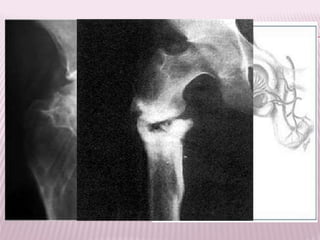

 Pacientes con fracturas intracapsulares, se

recomienda:

 Proyecciones radiográficas: Anteroposterior con

rotación medial de 15° del lugar afectado. Axial

de la cadera afectada

 Debe solicitarse:

 Radiografía de pelvis con rotación interna de la

cadera sana, lo que permite valorar la longitud real

del cuello femoral.

 Radiografía de la cadera fracturada, en lo posible

con rotación interna.

TRATAMIENTO

Fracturas

intracapsulares no

desplazadas

Osteosíntesis

Movilización precoz del paciente

y reduce el riesgo de

desplazamiento.

Tornillos tirafondo

canulados

 Pacientes mayores de 80 años, expectativa de vida

inferior a los 3 años.

Hemiartroplastía

Evitar el riesgo de

desplazamiento,

permitir una carga

precoz